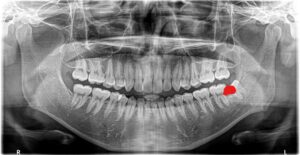

上のX線の患者さんは写真の左下の親知らず(正面から見て右下)が大きな虫歯になっており、手前の第二大臼歯もその影響で虫歯になっていました

赤い部分が虫歯です